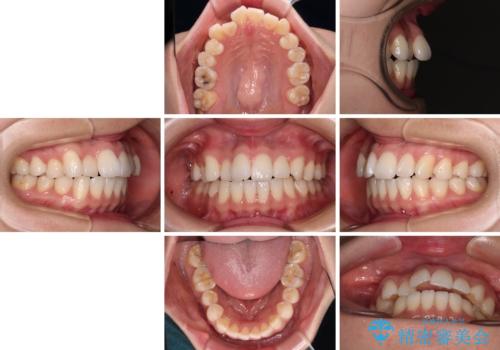

- 前歯のデコボコと、上下前歯が接触せずに前に飛び出していることを気にして来院された患者様です。

舌の突出癖が強く、それが原因で上顎歯列全体が前方に突出し、上下前歯が接触できない状態となっていました。